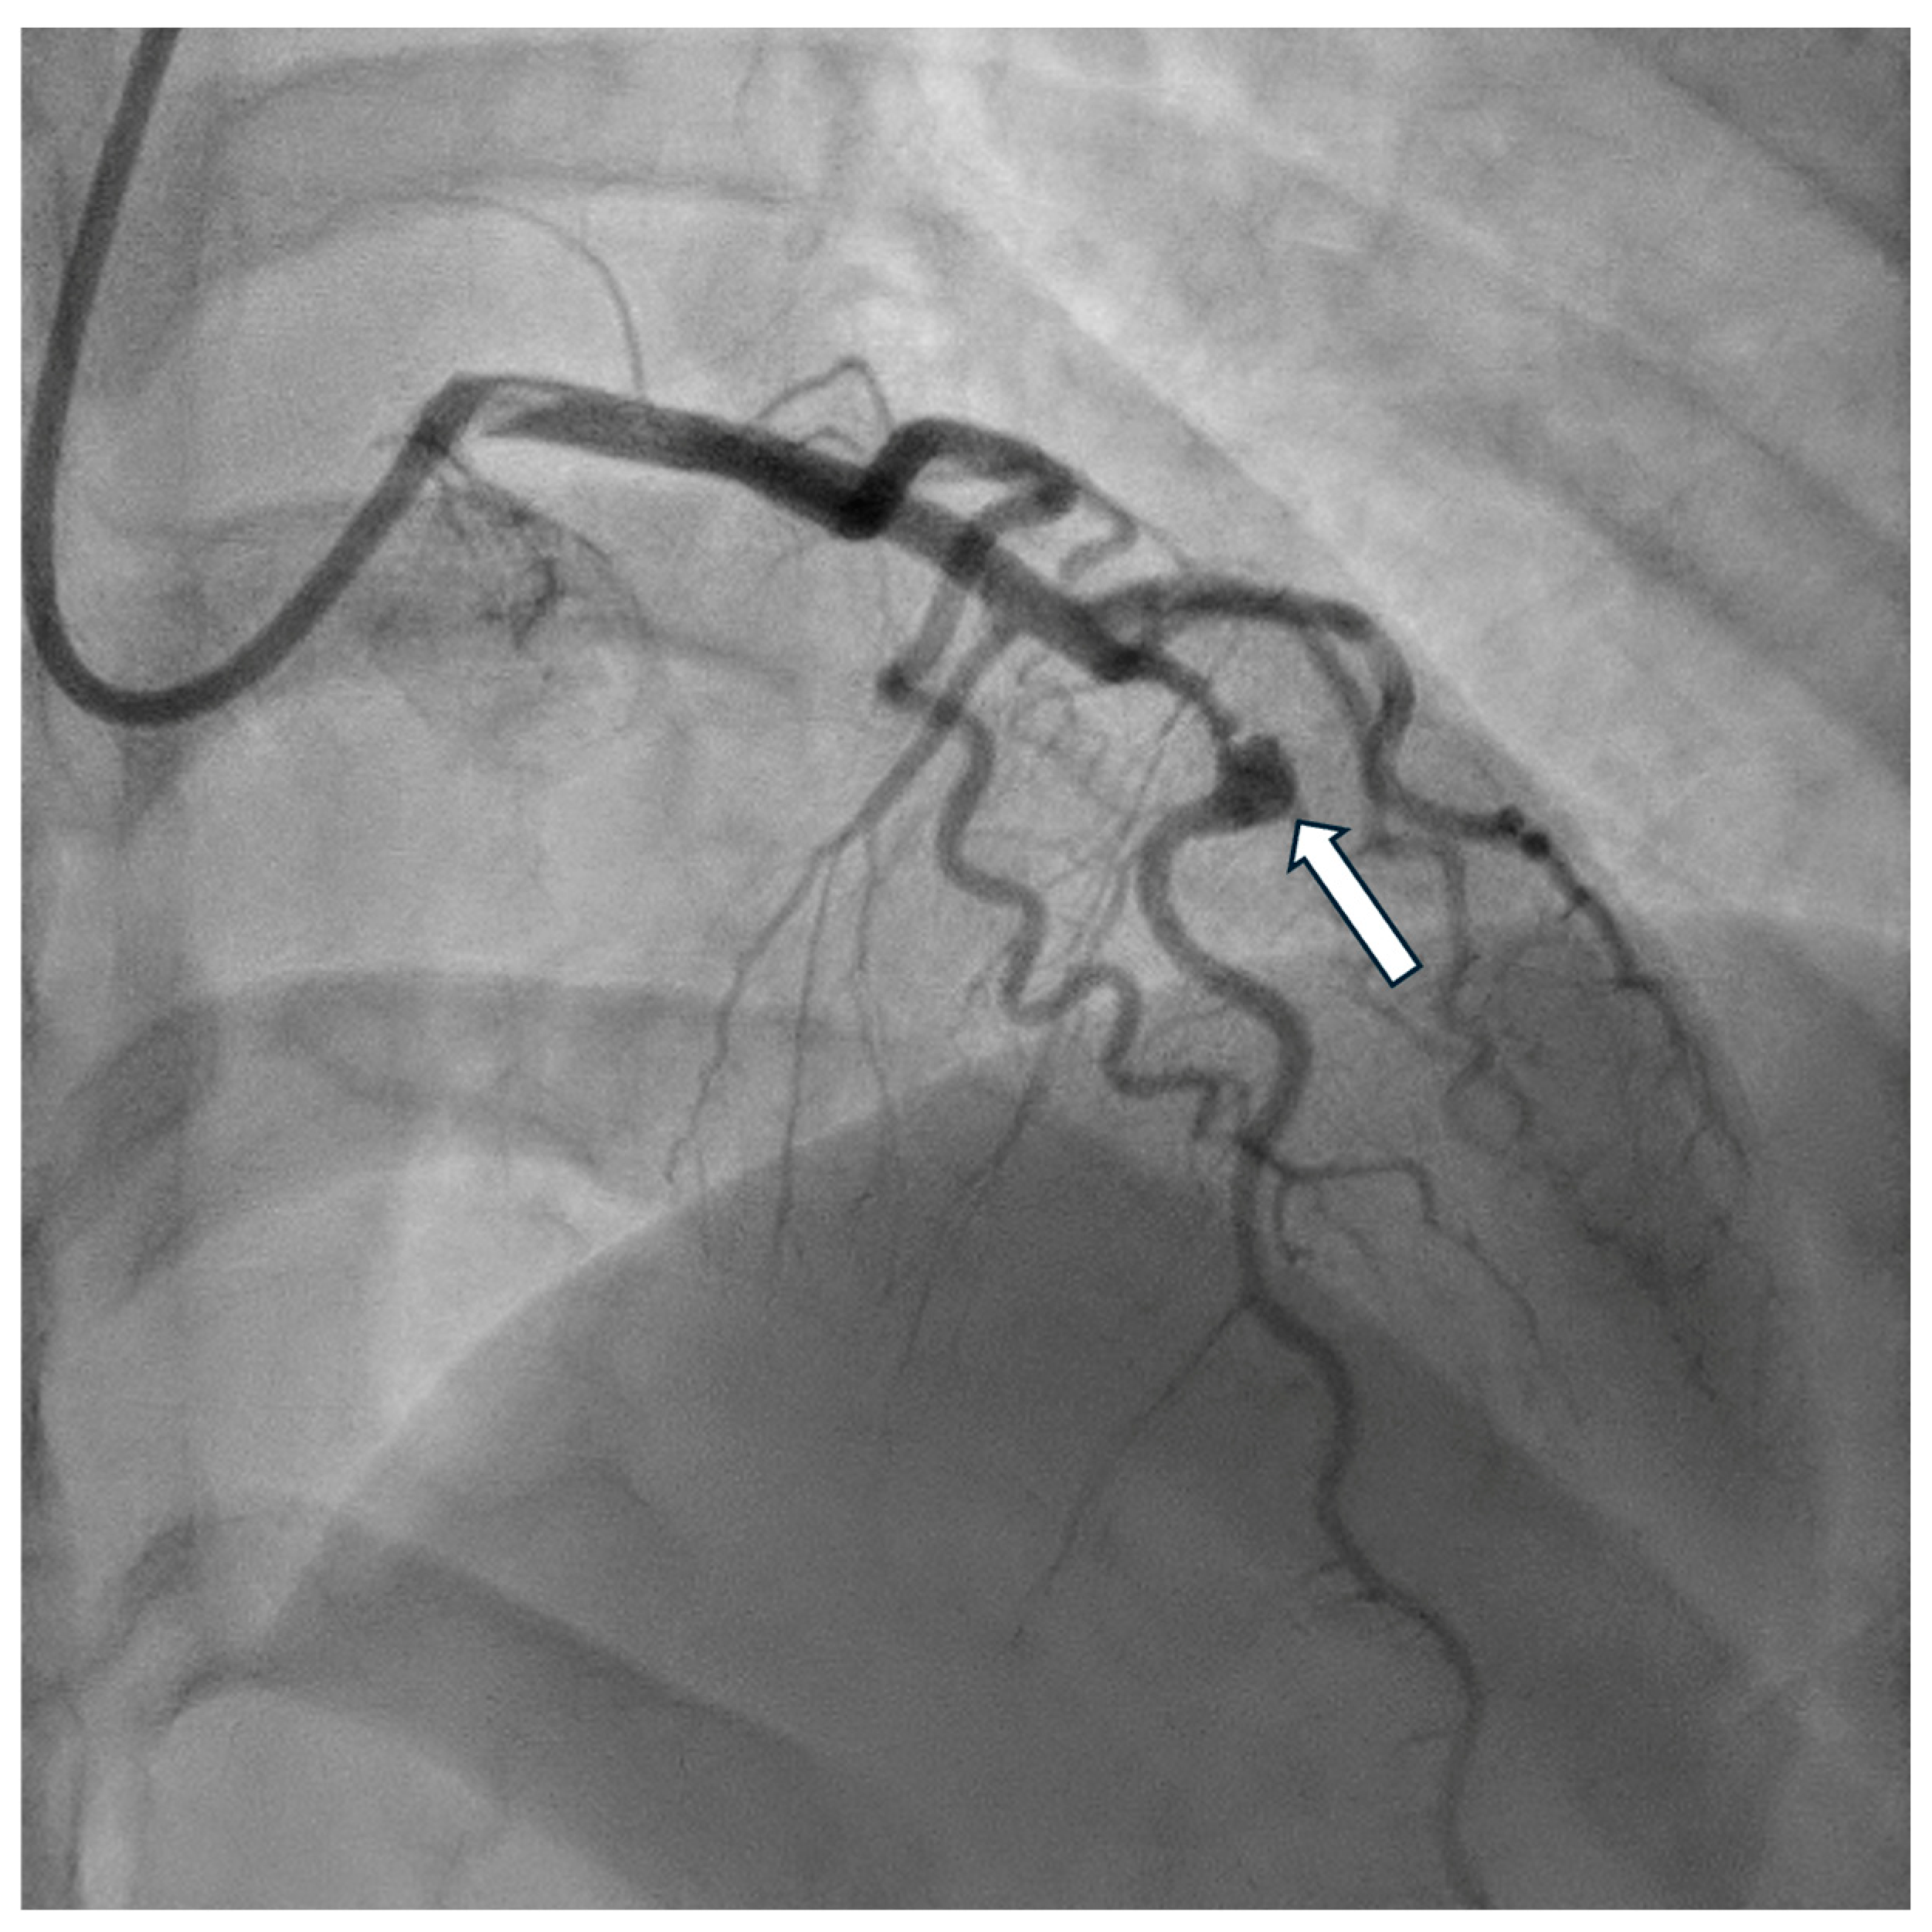

4. Diagnostics